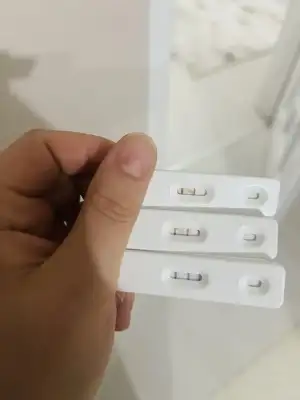

merhaba aranızda hiç ovülasyon veya çatlama gününde göğüslerinde kırmızı çatlak izleri oluşan oldu mu? ben en az 2 kez buna denk geldim ve lh testi ile doğruladım. beyaz çatlak izlerim zaten hep vardı ama ovülasyon gününde kıpkırmızı olup ertesi gün tekrar beyaz oluyorlar. böyle bir şey yaşayan var mı? :)